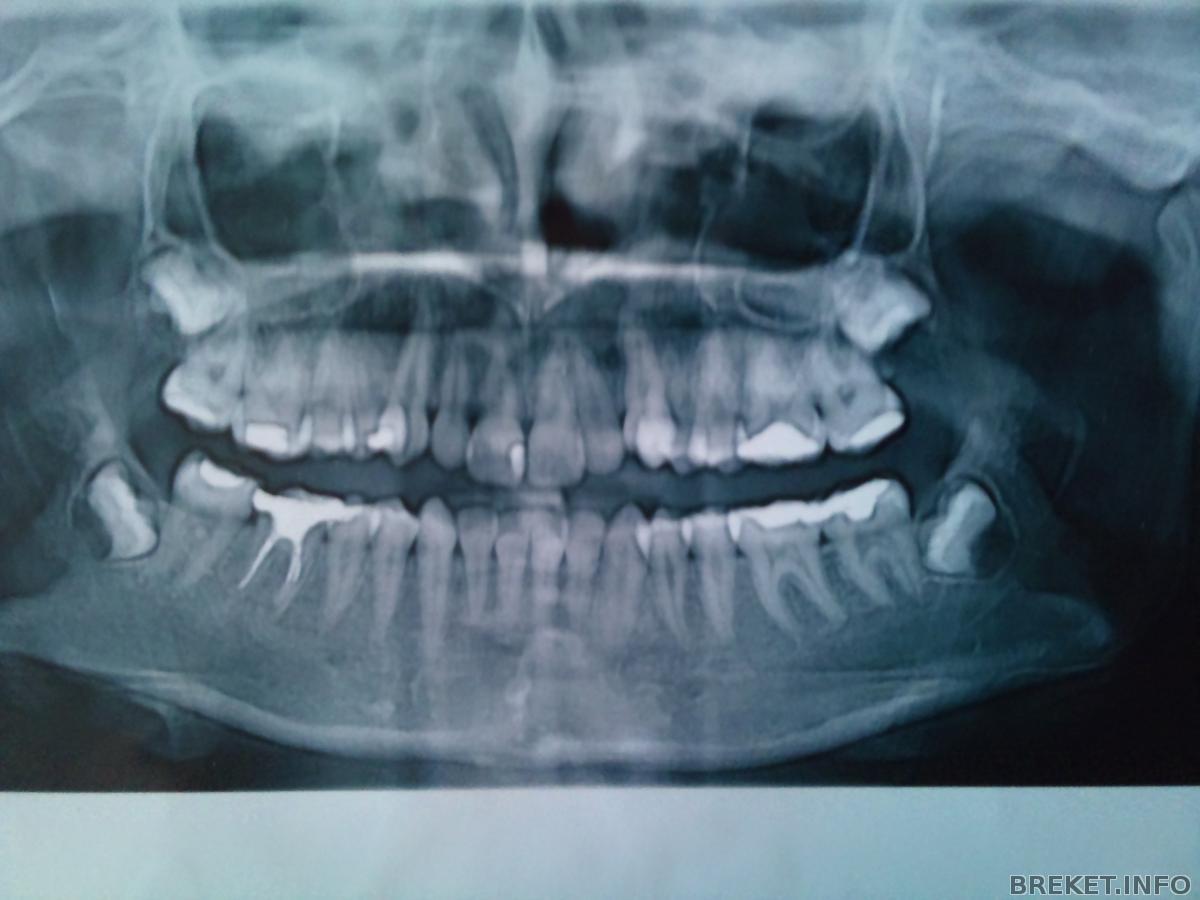

Вот еще фото прикрепила,правда не знаю зачем ))))

dsc_0205.jpg